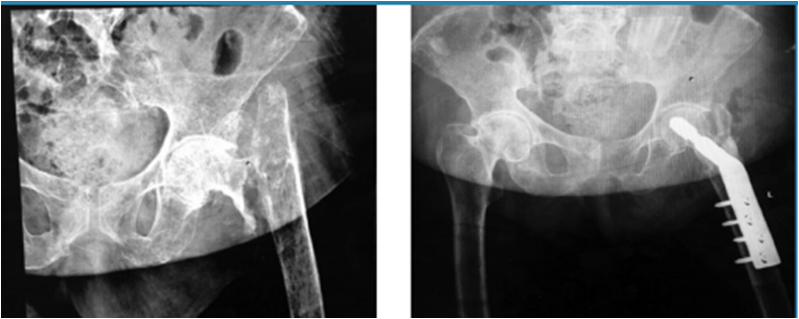

· 3 pacientes con fracturas de tercio distal de fémur supraintercondíleas con gran defecto óseo, para las cuales se utilizó placa condilar bloqueada en todas, se usó en un paciente 30 cc de aloinjerto de chip de esponjosa y en 2 aloinjerto de 60 cc de chip esponjosa (Fig. 2 y 3).

· 5 pacientes con pseudoartrosis, 3 correspondientes a meseta tibial a quienes se realizó osteosíntesis con placa de soporte en L y aloinjerto de chip de esponjosa 50 cc, 2 de fémur distal resueltas con placa condilar bloqueada con 60 cc de chip esponjosa y un paciente con fatiga de material de osteosíntesis (Fig. 4 y 5).

La consolidación fue definida mediante radiografía evaluando la estabilidad y callo formado, de las 7 fracturas pertrocantéricas 6 de ellas se les hizo un seguimiento por 8 meses con estudios radiológicos mensuales donde en los últimos controles se observaron signos de consolidación completa, con continuidad de corticales y paso de trabéculas en la zona medular, uno de ellos no se realizó seguimiento por pérdida de contacto con el paciente, el promedio de hospitalización fue de 10 días (8 - 40 días) todos con evolución favorable de la herida quirúrgica, solo uno de ellos debido a fractura expuesta Gustilo IIIB con herida a nivel de glúteo que requirió de limpiezas quirúrgicas en 6 ocasiones y se utilizó sistema VAC, una vez con mejoría de partes blandas se realizó la osteosíntesis definitiva.